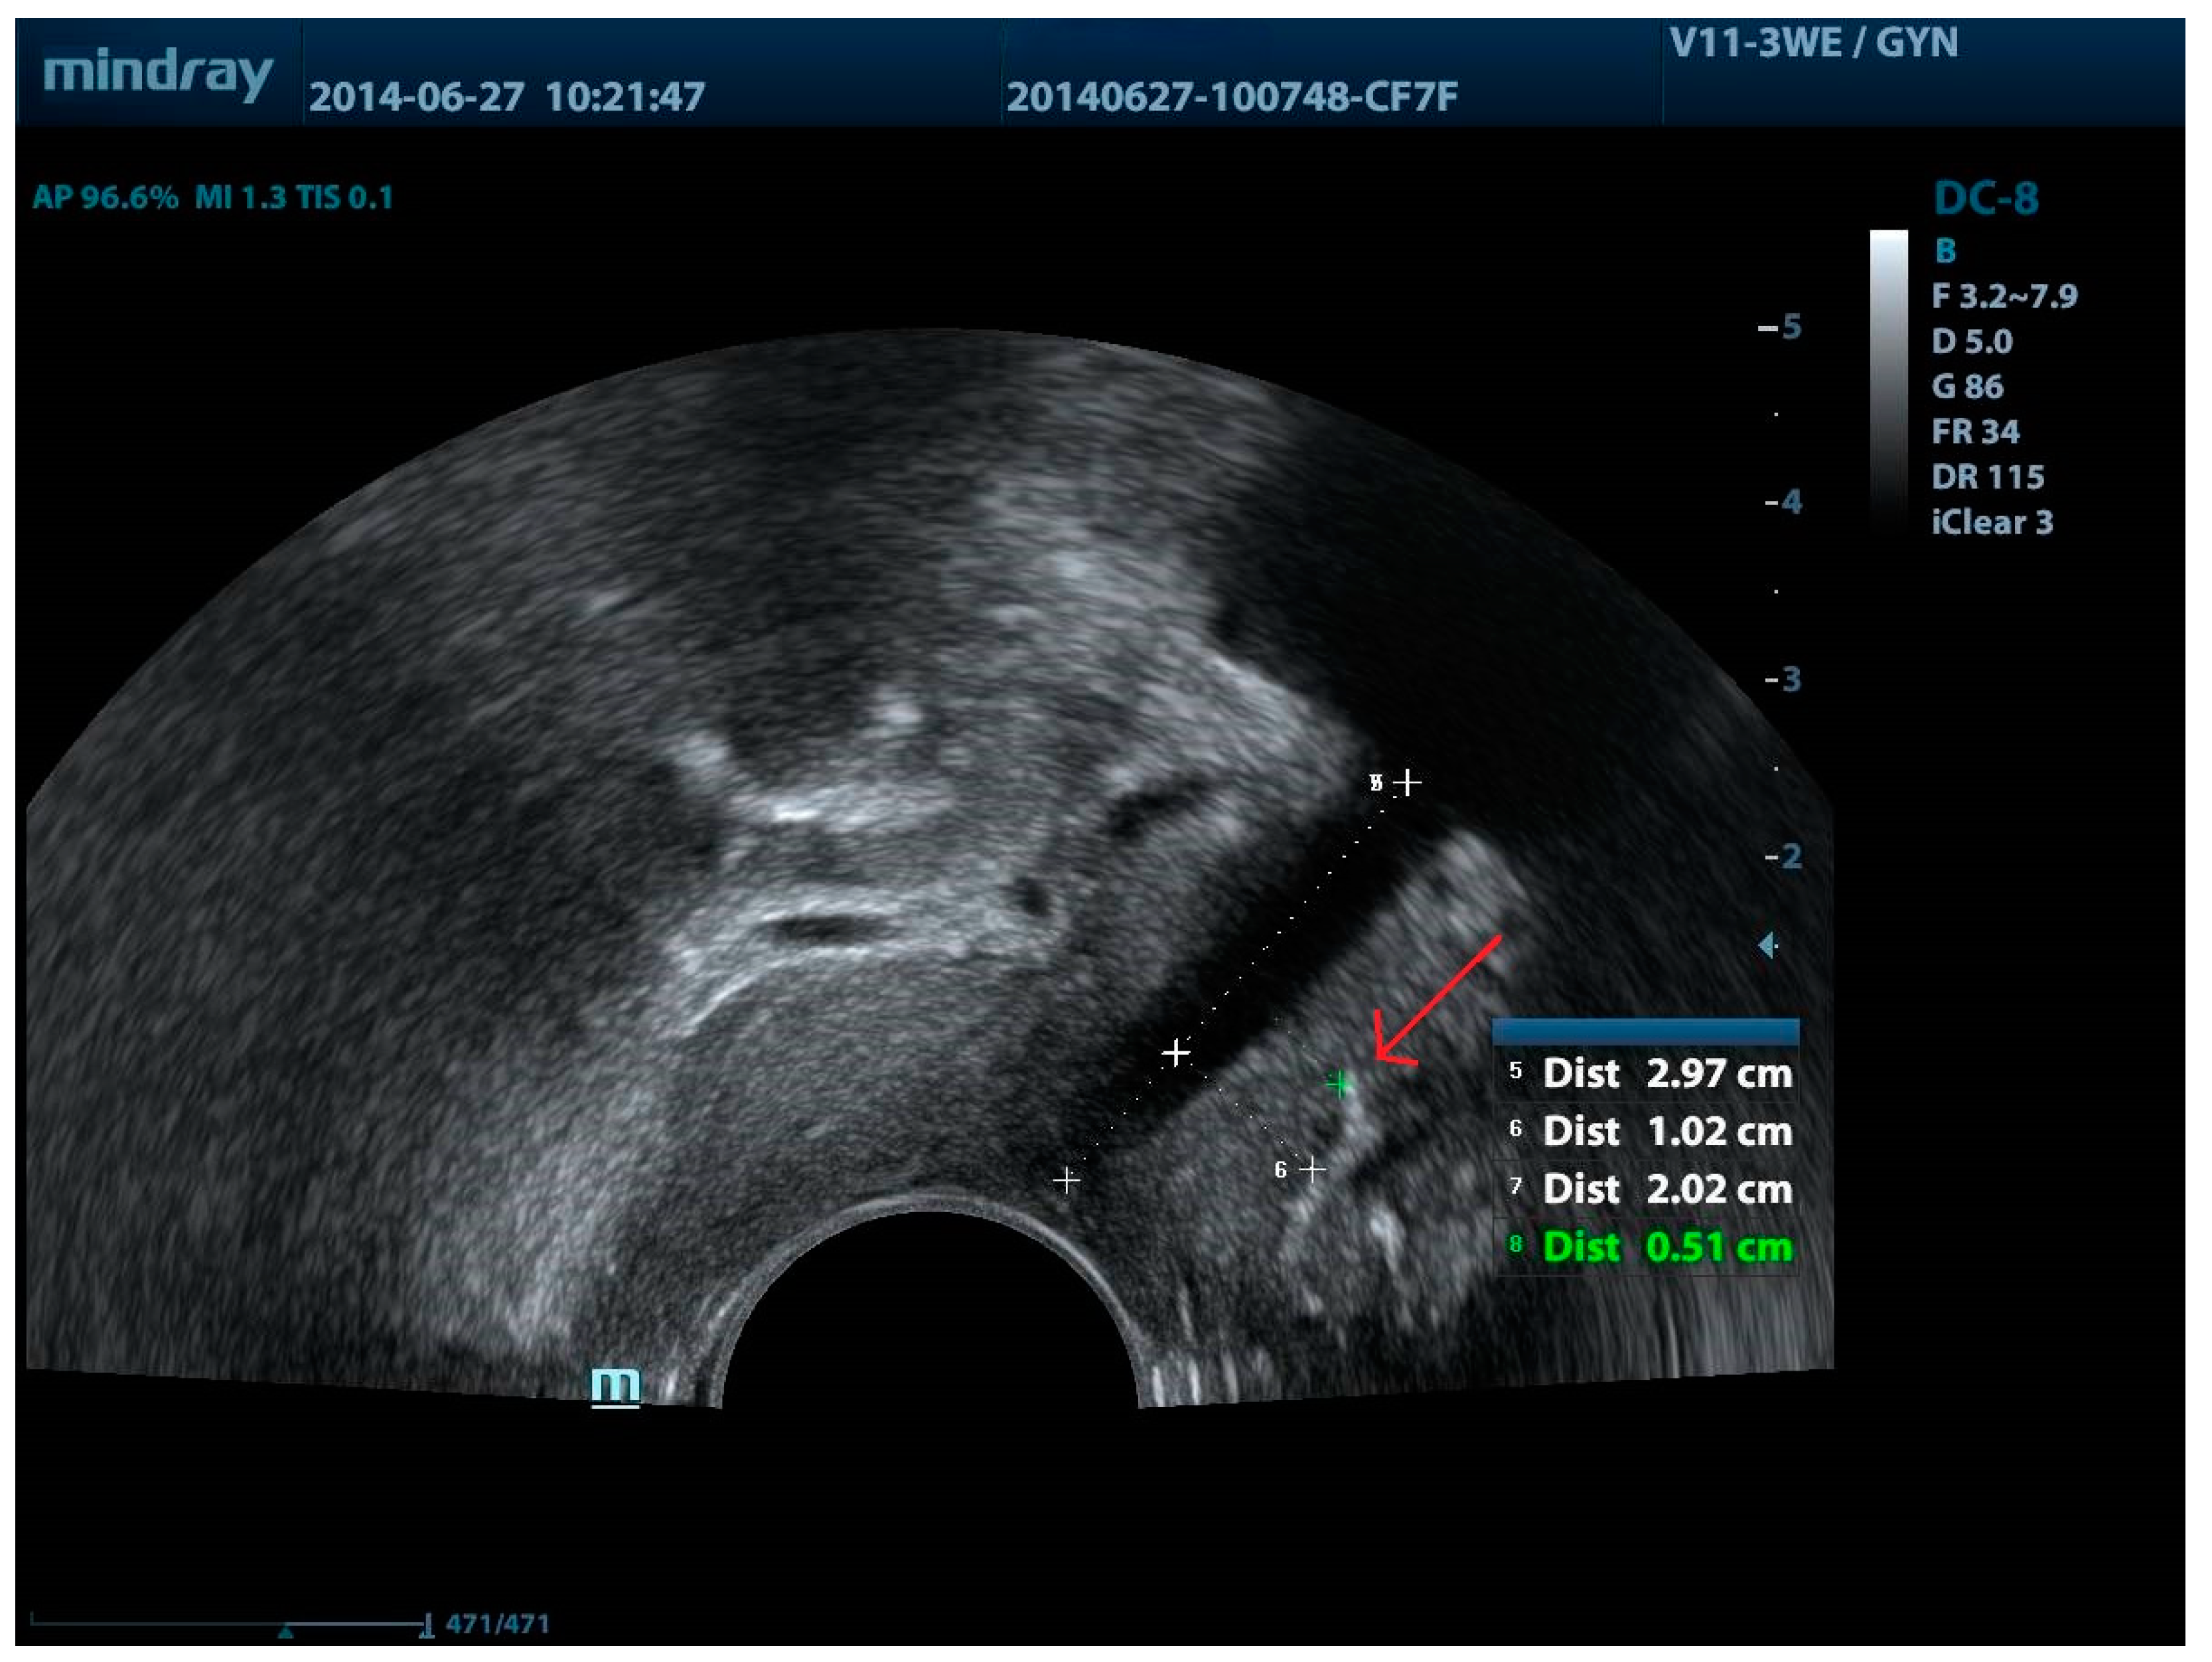

| Sling erosion | Lou et al., 2023 [87] | A case of sling erosion into the bladder with formation of secondary bladder stones. |

| Viragh et al., 2018 [88] | US could detect erosions not visible in cystourethroscopy. | |